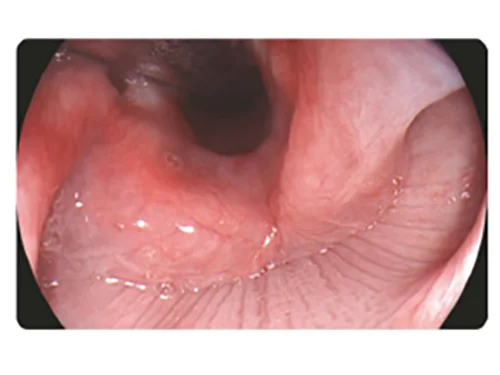

TEI: Визуализация с улучшением текстуры и цвета

Улучшение текстуры и цвета наряду со сбалансированной однородностью яркости подчеркивает контуры структур, повышает четкость изображения, позволяет улучшать видимость мелких и плоских образований.

Применение

- Диагностика воспалений и плоских блюдцеобразных поражений

- Изучение морфологии слизистой оболочки для обнаружения поражений.

Белый свет

TEI